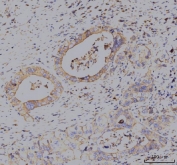

IHC staining of FFPE human lung cancer tissue with KCNQ1 antibody. HIER: boil tissue sections in pH8 EDTA for 20 min and allow to cool before testing.